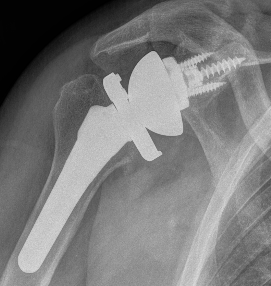

Xray

Template size and fit of glenoid & humeral components